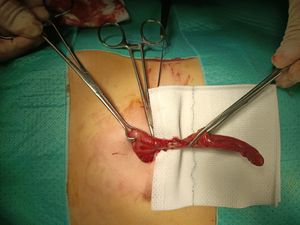

충수 절제술은 개복 수술 또는 복강경 수술을 통해 수행할 수 있다. 복강경 충수 절제술은 급성 충수염에 대한 중재로서 개복 충수 절제술보다 여러 가지 장점이 있다.[89]

개복술(개복 충수 절제술)은 100년 이상 급성 충수염의 표준 치료법이었다.[90] 이 수술은 하복부 오른쪽 부위에 단일 절개를 가하여 감염된 충수를 제거하는 방식으로 진행된다.[91] 개복술 시 절개 부위는 보통 약 5.08cm 에서 약 7.62cm 정도이다.

개복 충수 절제술 중에는, 충수염이 의심되는 환자는 근육을 완전히 이완시키고 의식을 유지하기 위해 전신 마취를 받는다. 절개 부위는 약 5.08cm 에서 약 7.62cm이며, 엉덩이뼈 위 몇 인치 지점의 오른쪽 하복부에 절개를 가한다. 절개를 통해 복강을 열고 충수를 확인한 후, 외과 의사는 감염된 조직을 제거하고 주변 조직에서 충수를 잘라낸다. 감염 부위를 주의 깊게 면밀히 검사하여 주변 조직에 손상이나 감염의 징후가 없는지 확인한다. 응급 개복 충수 절제술로 관리되는 복잡한 충수염의 경우, 복부 배액(농양 형성을 방지하기 위해 복부에서 외부로 연결하는 임시 튜브)을 삽입할 수 있지만, 이로 인해 입원 기간이 길어질 수 있다.[92] 외과 의사는 절개 부위를 봉합하기 시작한다. 이는 근육을 꿰매고 수술용 스테이플러 또는 봉합사를 사용하여 피부를 봉합하는 것을 의미한다. 감염을 예방하기 위해 절개 부위는 멸균 붕대 또는 수술용 접착제로 덮는다.